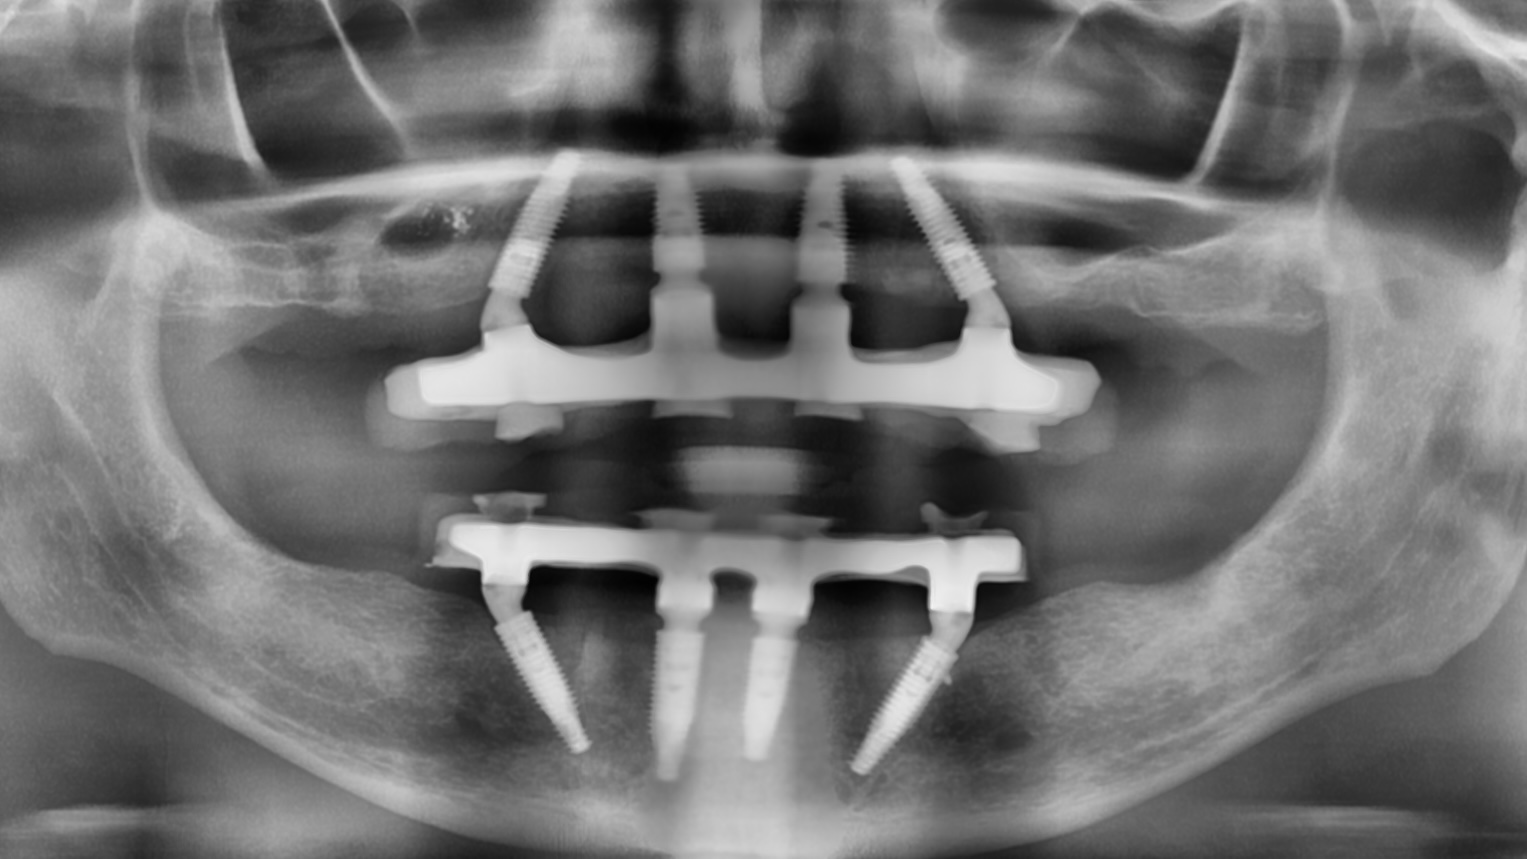

На данном этапе врач проводит визуальный осмотр полости рта, определяет состояние костной ткани и оценивает возможность имплантации. Чтобы получить развернутую картину клинической ситуации, делается рентгеновский снимок или КТ (компьютерная томография) челюсти.

Метод All-on-4 («всё на четырёх») — это протокол восстановления зубного ряда, при котором зубной протез фиксируется на четырёх имплантатах. Два имплантата устанавливаются вертикально во фронтальном отделе челюсти, ещё два — под углом в боковых (жевательных) зонах.

Протез фиксируется к имплантатам с помощью винтов и относится к условно-съёмным конструкциям: снять его может только врач. Метод позволяет восстановить жевательную функцию даже при выраженной атрофии костной ткани и часто не требует проведения синус-лифтинга.

All-on-6

Метод All-on-6 («всё на шести») предполагает установку шести имплантатов, которые служат опорой для несъёмного либо условно-съёмного протеза. Как правило, четыре имплантата устанавливаются вертикально, а два — под углом в боковых отделах челюсти.

Использование большего количества опор обеспечивает более равномерное распределение жевательной нагрузки и повышает общую стабильность ортопедической конструкции.